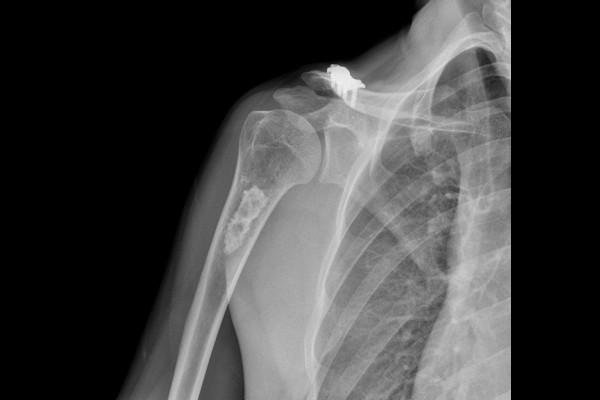

34세 남성 환자분께서 우측 어깨 상완골 부위 혹, 또는 종양 의심으로 내원해주셨습니다. 어깨 부위 혹을 발견하신 것은 약 한달정도 되었다고 하셨으며, 근처 병원을 먼저 방문하시어 X-RAY 및 MRI 검사 후 수술적 치료 소견을 들었으나, 수술범위가 커서 망설이던 도중, 제게 2~3년 전에 무릎 수술을 받으셨던 환자분의 아버님 소개로 저를 찾아오셨다고 말씀하셨습니다.

특이사항으로는 약 20년 전, 중학교 1학년 정도의 나이 때 혹, 종양이 의심되는 우측 어깨 상완골 동일 부위에 골절이 된 적이 있었습니다.

환자분께서 지참해오신 X-RAY를 확인했을 때 뼈 안에 음영이 다른 부분이 확인됩니다.